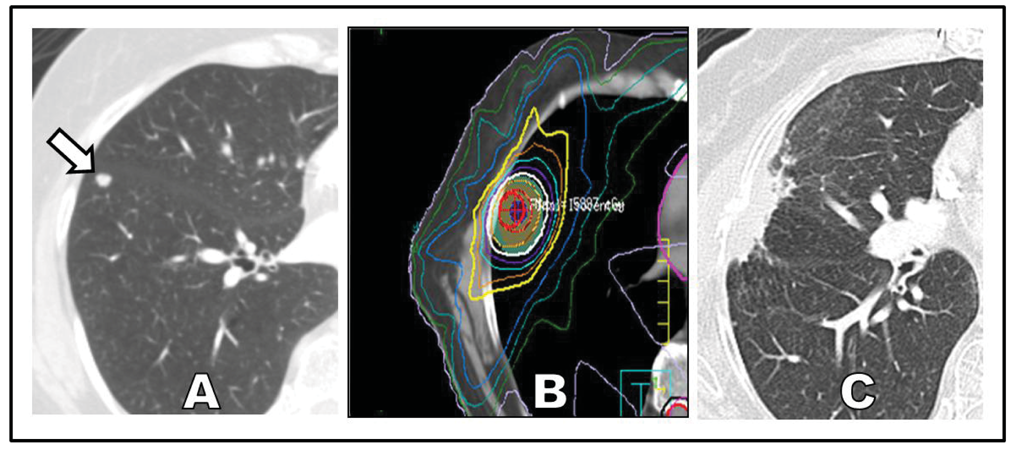

If delivered properly, SABR can offer definitive treatment for patients with poor performance status who are newly diagnosed with early-stage NSCLC (Figure 1). Two reasons account for the enthusiastic and broad adoption of SABR over invasive surgery for this specific clinical setting. First, the median age of patients with NSCLC is 71 years, making this a disease that predominantly affects elderly patients who are likely to have coincident chronic illnesses [19]. Second, the most prevalent risk factor for lung cancer is chronic smoking, and chronic smoking carries the parallel risks of multiple systemic medical conditions, including chronic obstructive pulmonary disease [20,21], coronary artery disease [22-24], cerebrovascular disease [25], chronic renal insufficiency [26], and a number of other malignancies [27].

A different kind of challenge in the use of SABR is the delineation of proper follow-up after treatment has occurred. Parenchyma changes such as fibrosis and persistent radiation pneumonitis can occur following SABR, and the resultant radiographic appearance on surveillance CT imaging can run the gamut from diffuse consolidation and ground-glass opacities to focal consolidation and scarring. In some cases, focal consolidation during follow-upis hard to distinguish from tumor recurrence (Figure 1C). This wide spectrum of radiographic changes can render tools like the RECIST criteria insufficient for evaluation of local response. Moreover, PET as a means to distinguish postradiation effects from viable tumor is problematic, as treated regions can have persistent [18F ] fluorodeoxyglucose avidity for up to a year following SABR [72,73]. More recent studies suggest that specific findings on PET such as a high post-SABR standardized uptake volume (>5) more than 3 months after SABR can better select the best patients for biopsy to confirm recurrence [74]. Despite these diagnostic challenges, a lack of clear progression of a tumor following treatment is a positive sign, and an experienced radiologist familiar with post-SABR effects should be able to distinguish between SABR effects and tumor recurrence. Identifying recurrence is important as emerging studies suggest that salvage surgery following SABR may be feasible [75]. Future studies are expected to illuminate these controversial areas and provide evidence-based guidance for surveillance and, if necessary, salvage therapy after SABR.